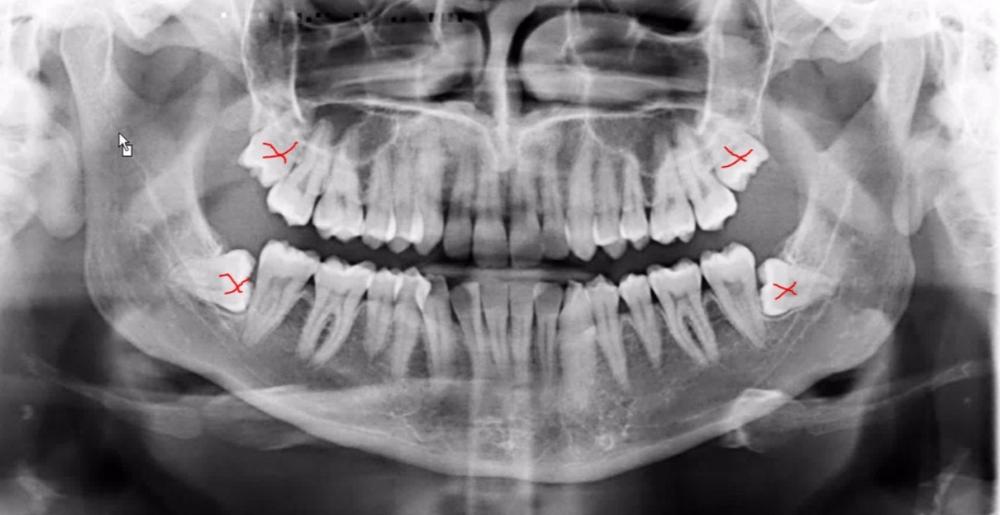

Below are examples of a few sets of surgeries that we routinely perform: